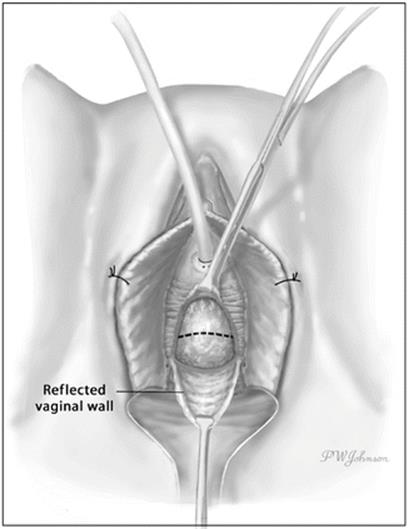

A distinct layer of periurethral fascia is usually interposed between the vaginal wall and the UD. Preservation and later reconstruction of this layer is of paramount importance to prevent recurrence, close dead space, and avoid urethro-vaginal fistula formation postoperatively. Pseudodiverticula have been described where this layer of tissue is considerably attenuated or even absent [58]. In these patients, an interpositional flap or graft such as a pubovaginal sling may be utilized for reconstruction.

The periurethral fascia is incised transversely (Fig. 11.7). Proximal and distal layers of periurethral fascia are carefully developed using Metzenbaum scissors, avoiding entrance into the UD. The UD is then grasped and dissected back to its origin on the urethra within the leaves of the periurethral fascia (Fig. 11.8). In many cases it is necessary to open the UD to facilitate dissection from the surrounding tissues. The ostia or connection to the urethra is identified and the walls of UD are completely removed. Every effort should be made to remove the entire mucosalized surface of the UD in order to prevent recurrence [11, 59]. This may involve removing small adherent or inflamed portions of the urethral wall, especially in the area of the ostia. All abnormal tissue in the area of the ostia should be removed if possible to ensure that no mucosal elements of the UD wall remain which could result in postoperative urine leakage and recurrence. Elaborate methods of identifying the full extent of the UD cavity have been described including catheterization of the UD with urinary [12, 60] and Fogarty [61] catheters, packing the UD with gauze [62], infusing and staining the UD with methylene blue, and the use of silicone [63] or cryoprecipitate [64] to create a solid mass and ease dissection.

Fig. 11.7

After reflection of the anterior vaginal wall, a transverse incision is made in the periurethral fascia. The dotted line represents the intended incision line (Used with permission from Rovner ES. Urethral diverticula. In: Female Urology, 3rd ed. Edited by Raz S, Rodriguez LV. Philadelphia: Saunders Elsevier; 2008)